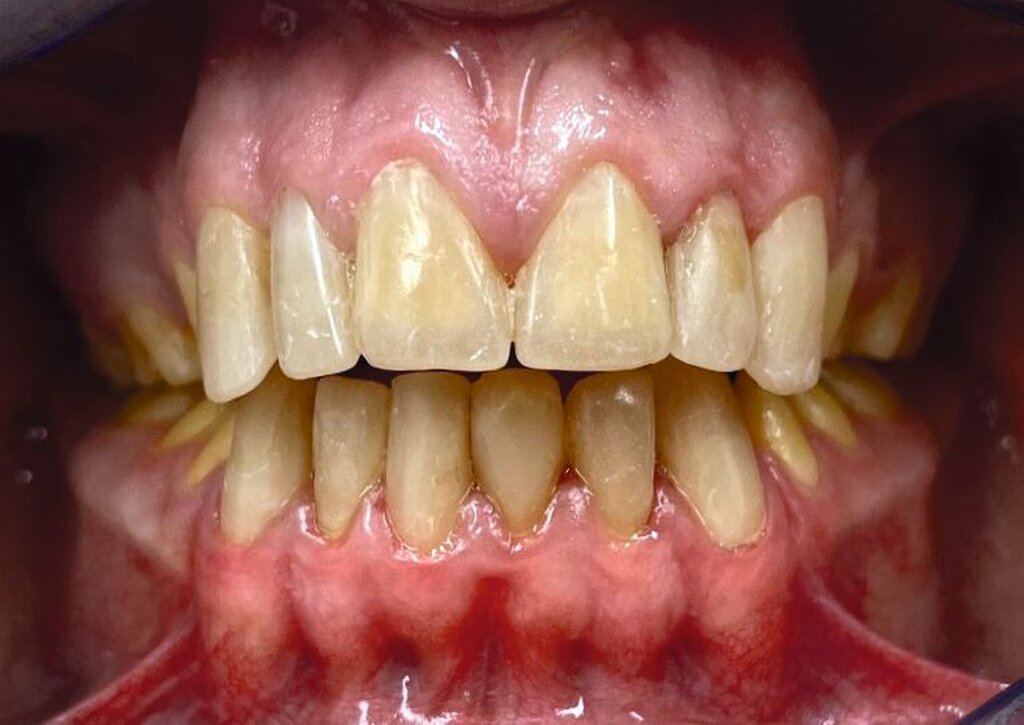

Die zu diesem Zeitpunkt seit fünf Jahren inserierten Frontzahnkronen zeigten Randverfärbungen sowie durch den Durchbruch entstandene Stufen zur natürlichen Zahnhartsubstanz (Abbildung 9). Diese wurden durch Sandstrahlen (CoJet, Solventum), anschließende Konditionierung mit einem Drei-Schritt-Etch-and-Rinse-System und Komposit (Filtek Supreme, Solventum; Tetric EvoFlow, Ivoclar Vivadent) korrigiert und abschließend poliert.